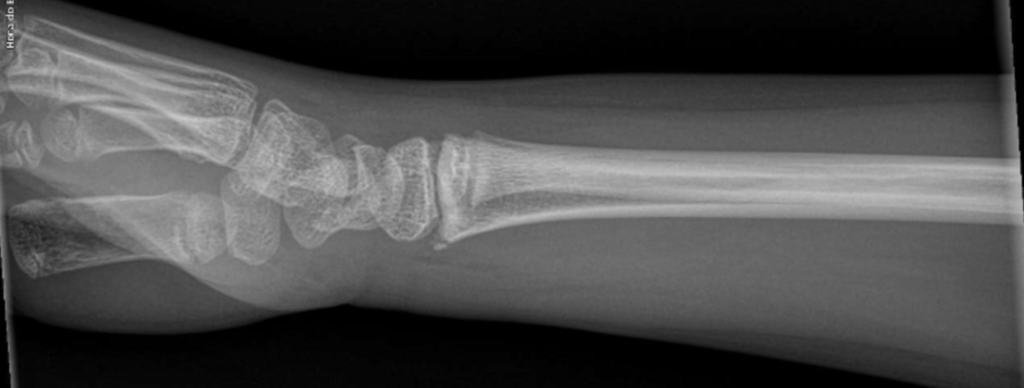

Fratura em “galho verde”